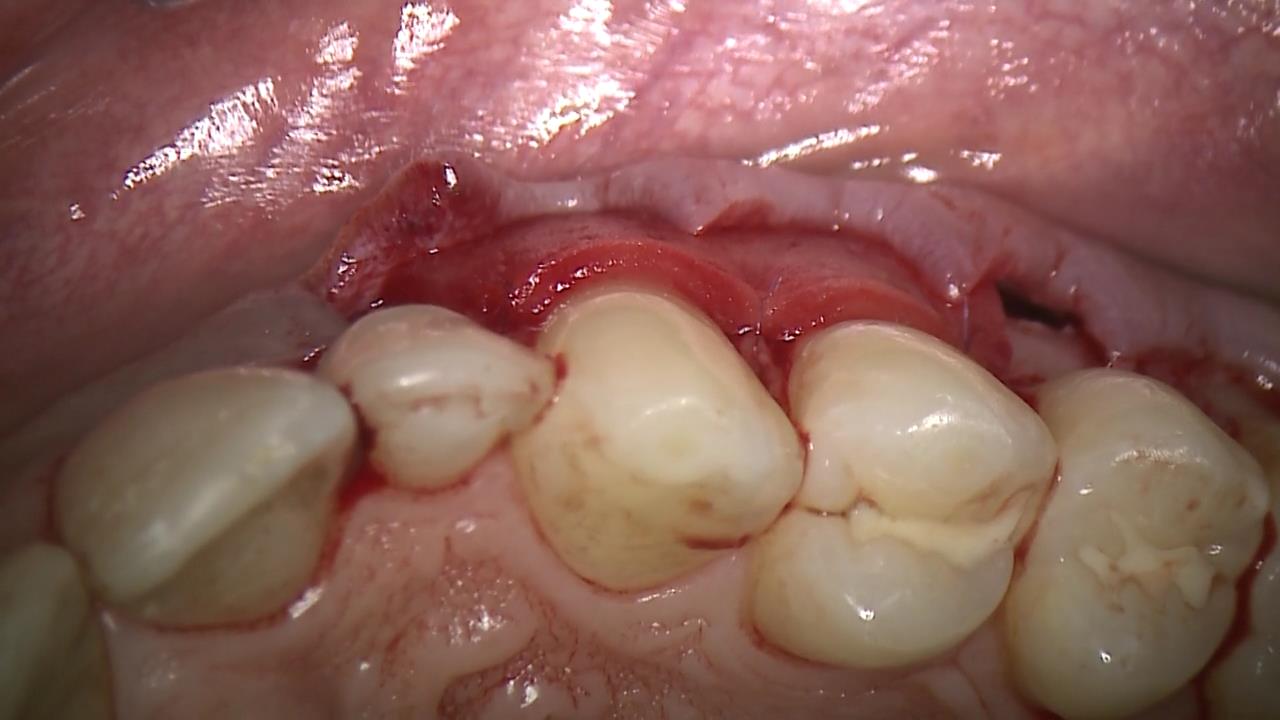

8/12 - Occlusal view of the sutured matrixMultiple recession coverage with mucoderm® and Straumann® Emdogain® - 4 year follow-up - Prof. G. Zucchelli & Dr. M. Stefanini

9/12 - Occlusal view after flap closure: note complete absence of bleedingMultiple recession coverage with mucoderm® and Straumann® Emdogain® - 4 year follow-up - Prof. G. Zucchelli & Dr. M. Stefanini